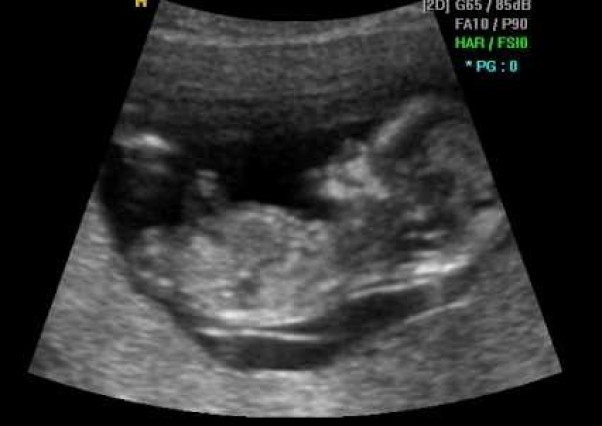

Witam ponownie po rocznej przerwie :P kilka miesięcy temu los zgotował nam niespodziankę i spodziewamy się 4 dzidziusia <3 aktualnie jestem w 15 tygodniu ciąży a termin porodu wypada na 8.03.2016 :)

poniżej zdjęcie naszej kruszyny z przed 3 tyg <#